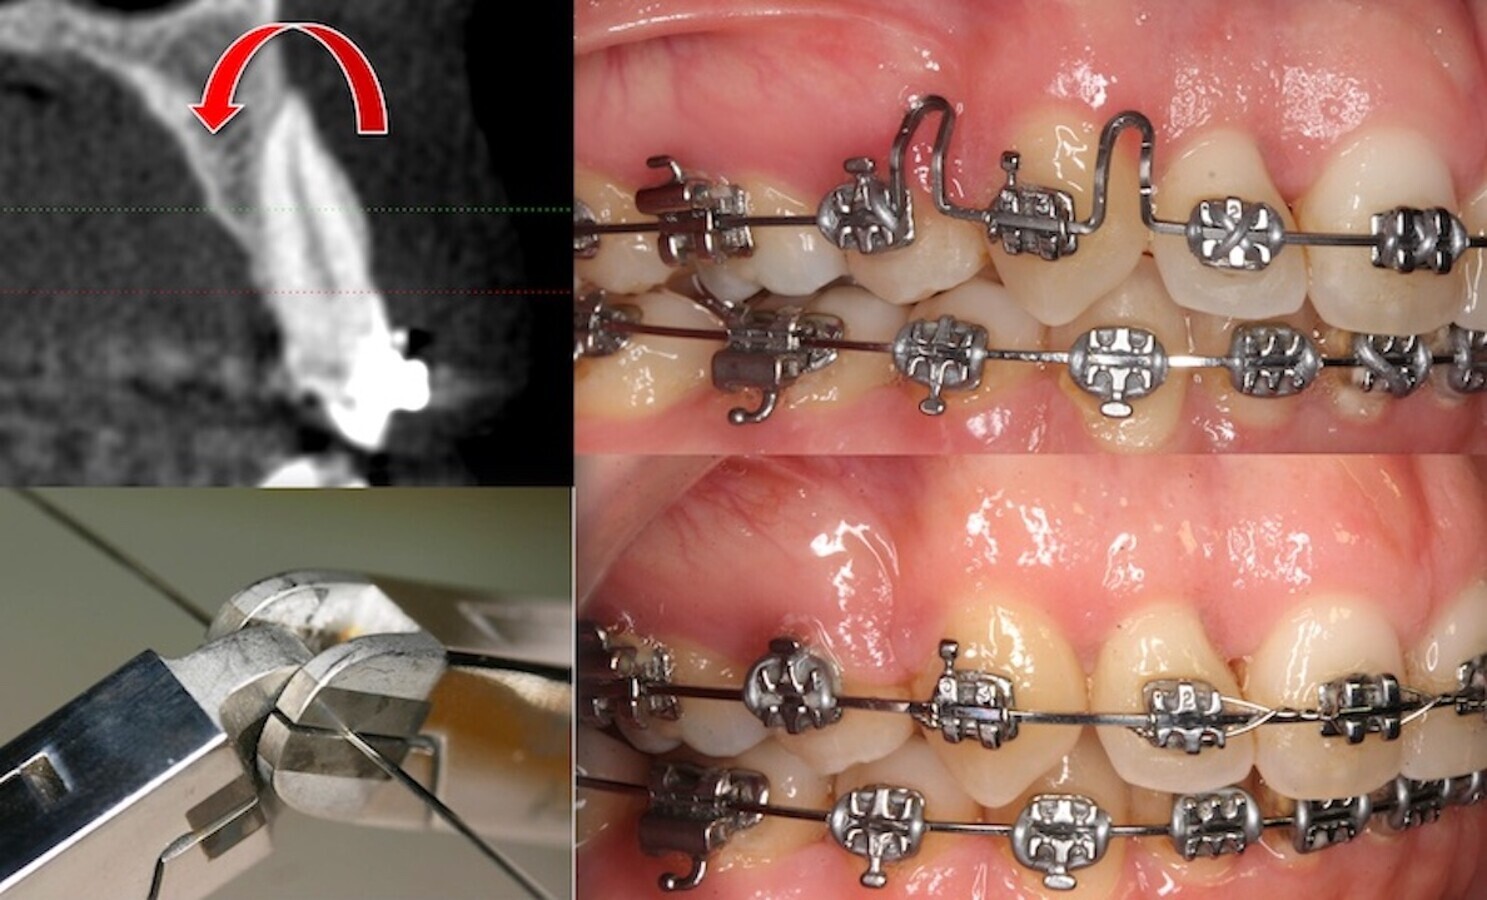

Figura 7. Expansión indiscriminada producida en la boca de la paciente, referida en el texto, con brackets y arcos “milagrosos”. El CBCT nos muestra como los incisivos, caninos y premolares están fuera de la cortical.

Me gusta decir en mis cursos que si hoy (gracias a los progresos tecnológicos, no biológicos) haces más del 20% de extracciones en tu consulta, deberías de cambiar de técnica, y si haces menos del 5%, deberías estudiar más ortodoncia. Una primera afirmación: las técnicas, con “brackets milagrosos” que prometen eliminar las extracciones son un engaño y gran parte de sus sorprendentes resultados se basan en una sobreexpansión indiscriminada que coloca a las raíces dentarias fuera de la cortical vestibular, condenando al paciente en pocos años a padecer un serio problema periodontal (tanto de dehiscencia y recesión como de reabsorción radicular externa); los resultados de estas técnicas milagrosas ya se empiezan a ver hoy en todas las clínicas2, 10-12.

Descripción de un caso

Una paciente acude a la consulta para una segunda opinión sobre su actual tratamiento de ortodoncia; refiere que está contenta con su ortodoncista, es más, que vio cómo sus dientes apiñados se alineaban muy rápidamente en los primeros meses del tratamiento. Ella decidió hacerse ese tratamiento en esa clínica porque en otras consultas le propusieron hacer, nada menos, que cuatro extracciones. El motivo del desconcierto actual de la paciente, y de la visita a nuestra clínica, es que desde hace más de un año, tras el alineamiento inicial, no ve progresos en el tratamiento, ahora “muerde mal” y la doctora apenas cambia arcos o hace algo en cada visita. Le mando realizar un CBCT de ambos maxilares y su resultado, desgraciadamente, no representa ninguna sorpresa para mí; los incisivos presentan una marcada proinclinación labial y la mayoría de las raíces se encuentran fuera de la cortical, siendo la situación especialmente grave a nivel del sector incisivo-canino. Es el resultado de la expansión indiscriminada con brackets “mágicos” de autocierre y arcos king-size con la forma y dimensiones de una plaza de toros (Figuras 7 y 8).